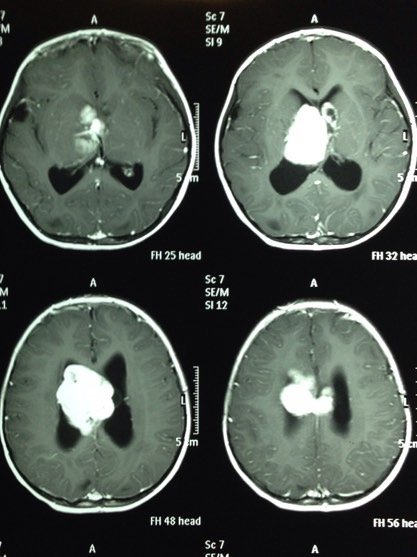

ESCLEROSIS TUBEROSA